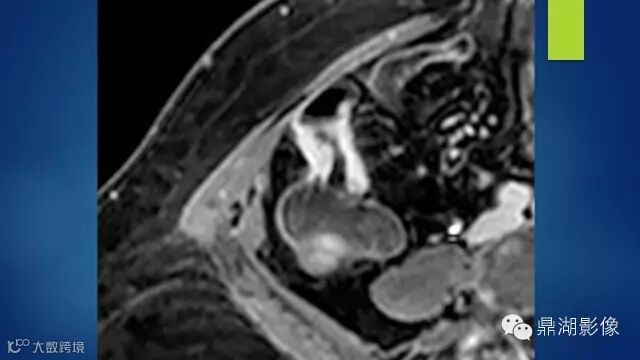

It is the comb sign the most specific sign for crohn's disease.

ULCer